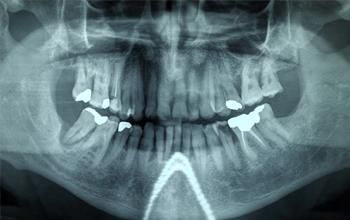

Ortopantomografía o panorámica dental

La ortopantomografía es una radiografía panorámica dental que plasma una imagen de todos los dientes superiores e inferiores de tu boca en un mismo soporte.